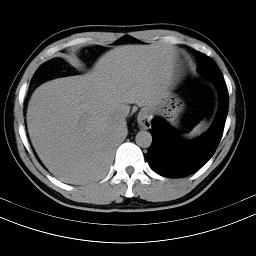

标题: CT18388:肝脏膈肌间隙内大量脂肪密度影 [打印本页]

标题: CT18388:肝脏膈肌间隙内大量脂肪密度影

考虑----气腹可能性大---进一步检查

是脂肪不是气体,有时候会碰到这样的病人,脂肪过多吧。

腹腔脂肪沉积过多

局部脂肪沉积。

膈下脂肪沉积。

考虑膈下脂肪沉积。

腹腔脂肪沉积症

激素治疗的病人容易脂肪沉积